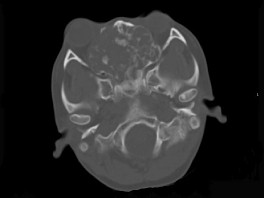

男性,28岁,因鼻塞、头痛1年余,鼻窦CT扫描如图所示,请选择正确的描述与结论 ( ) EBH-00091.jpg EBH-00092.jpg EBH-00093.jpg EBH-00094.jpg

• A.肿块内密度不均,有较多致密钙化影

• B.窦壁及颅底骨质破坏

• C.双侧上颌窦、筛窦、鼻腔及蝶窦内见软组织肿块影

• D.考虑为鼻窦软骨瘤

• E.考虑鼻窦骨瘤